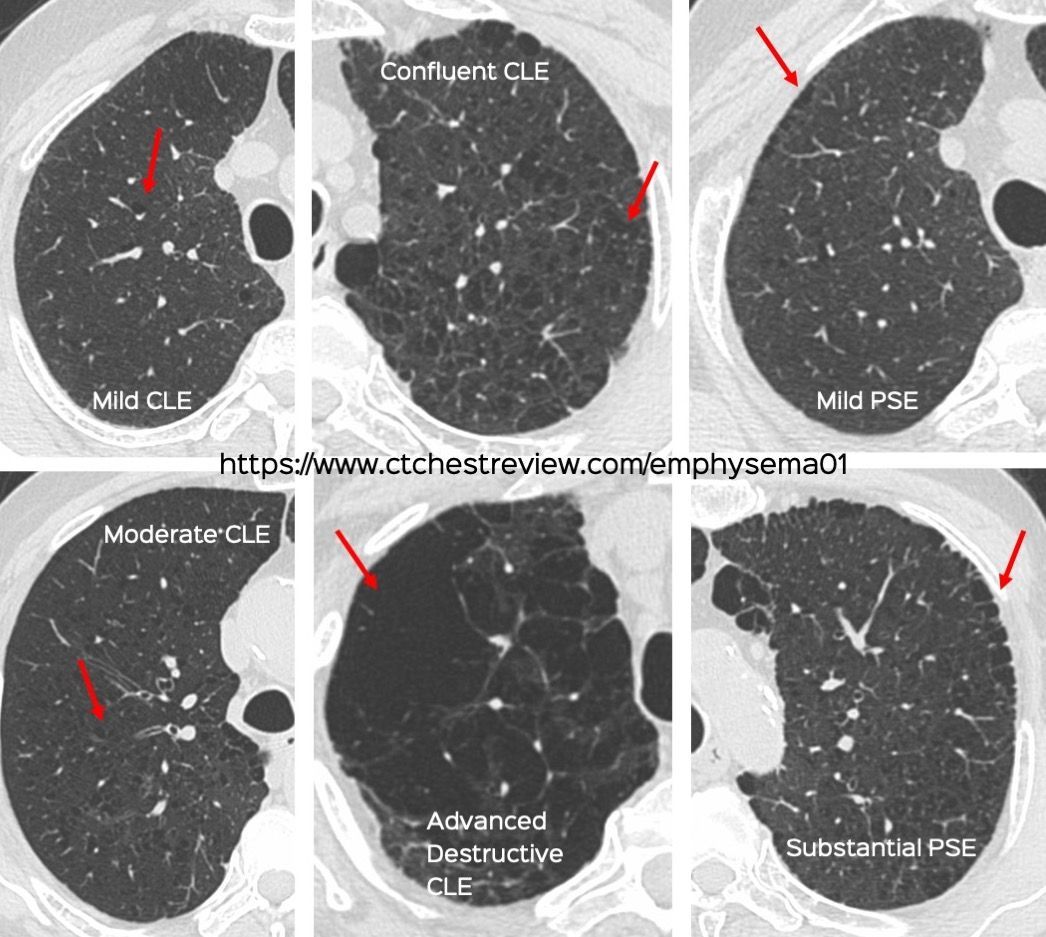

Snippet 12: Visual Classification of Centrilobular and Paraseptal Emphysema Members Public

Visual Classification of Centrilobular and Paraseptal Emphysema

Emphysema